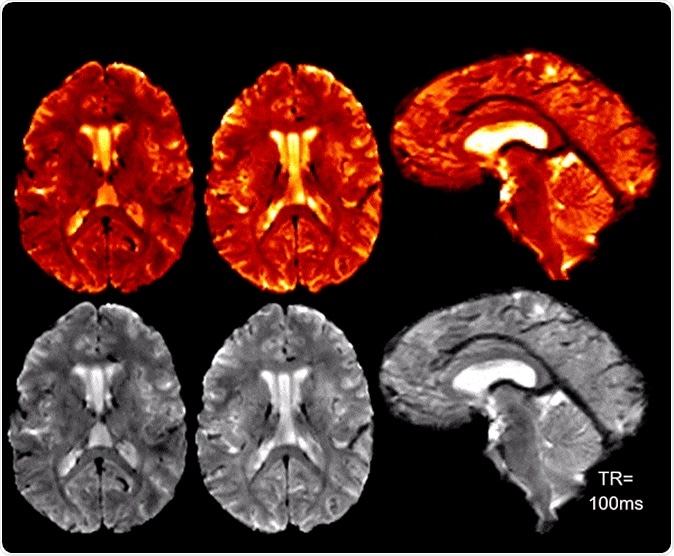

High SNR/CNR allows for real-time 7T MRI for brain pulsatility and CSF flow measurements. Credit: Radiofrequency (RF) Research Facility.